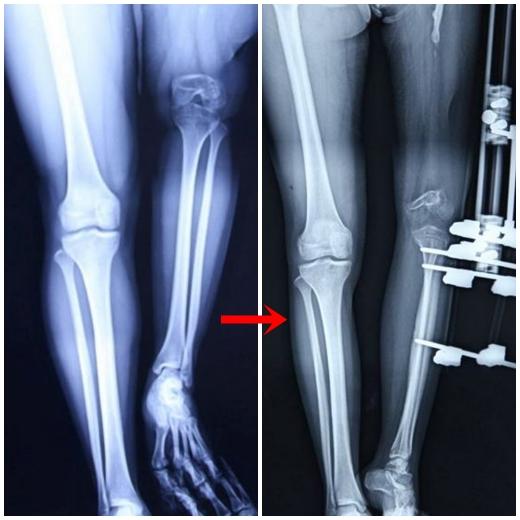

[아시아경제 온라인이슈팀] 박테리아 감염으로 오른쪽에 비해 현저히 짧은 왼쪽 다리를 가진 채 힘겹게 살아온 20대 중국여성이 최근 현대 의술의 도움으로 정상적인 걸음을 걷게 돼 화제다.

한창 외모 가꾸기에 바쁠 20대 초반 또래 여성들에 비해 유독 주안의 미소가 어두운 이유는 그녀의 남다른 신체구조 때문이었다. 바로 왼쪽 다리가 오른 쪽 다리에 비해 무려 23cm나 짧아 목발 없이는 제대로 걷지 못했다고 했다.

주안이 이렇게 된 사연은 어린 시절, 원인을 알 수 없는 박테리아들의 침투로 왼쪽 다리뼈가 감염된 적이 있다. 급히 동네 병원을 찾았지만 마땅한 약품을 찾지 못해 치료받지 못했고 그녀의 왼쪽 다리는 성장을 거의 하지 못한 채 방치됐다.

2012년 10월과 2013년 10월에 걸쳐 치료는 성공적으로 이뤄졌고 올 2월말 주안의 치료는 공식적으로 마무리됐다.